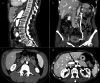

Fig. 8

Abdomen MDCT examination. a The reconstruction according to a sagittal plane shows the characteristic pattern with aorta and superior mesenteric artery "beak-like" appearance (black arrow). b The coronal plane reconstruction shows dilation of the gonadal vein and gonadal plexus (arrow). c The axial plane reconstruction shows a stenosis of duodenum (arrow). "D": Duodenum. d The axial plane reconstruction shows a stenosis of the left renal vein (arrow)